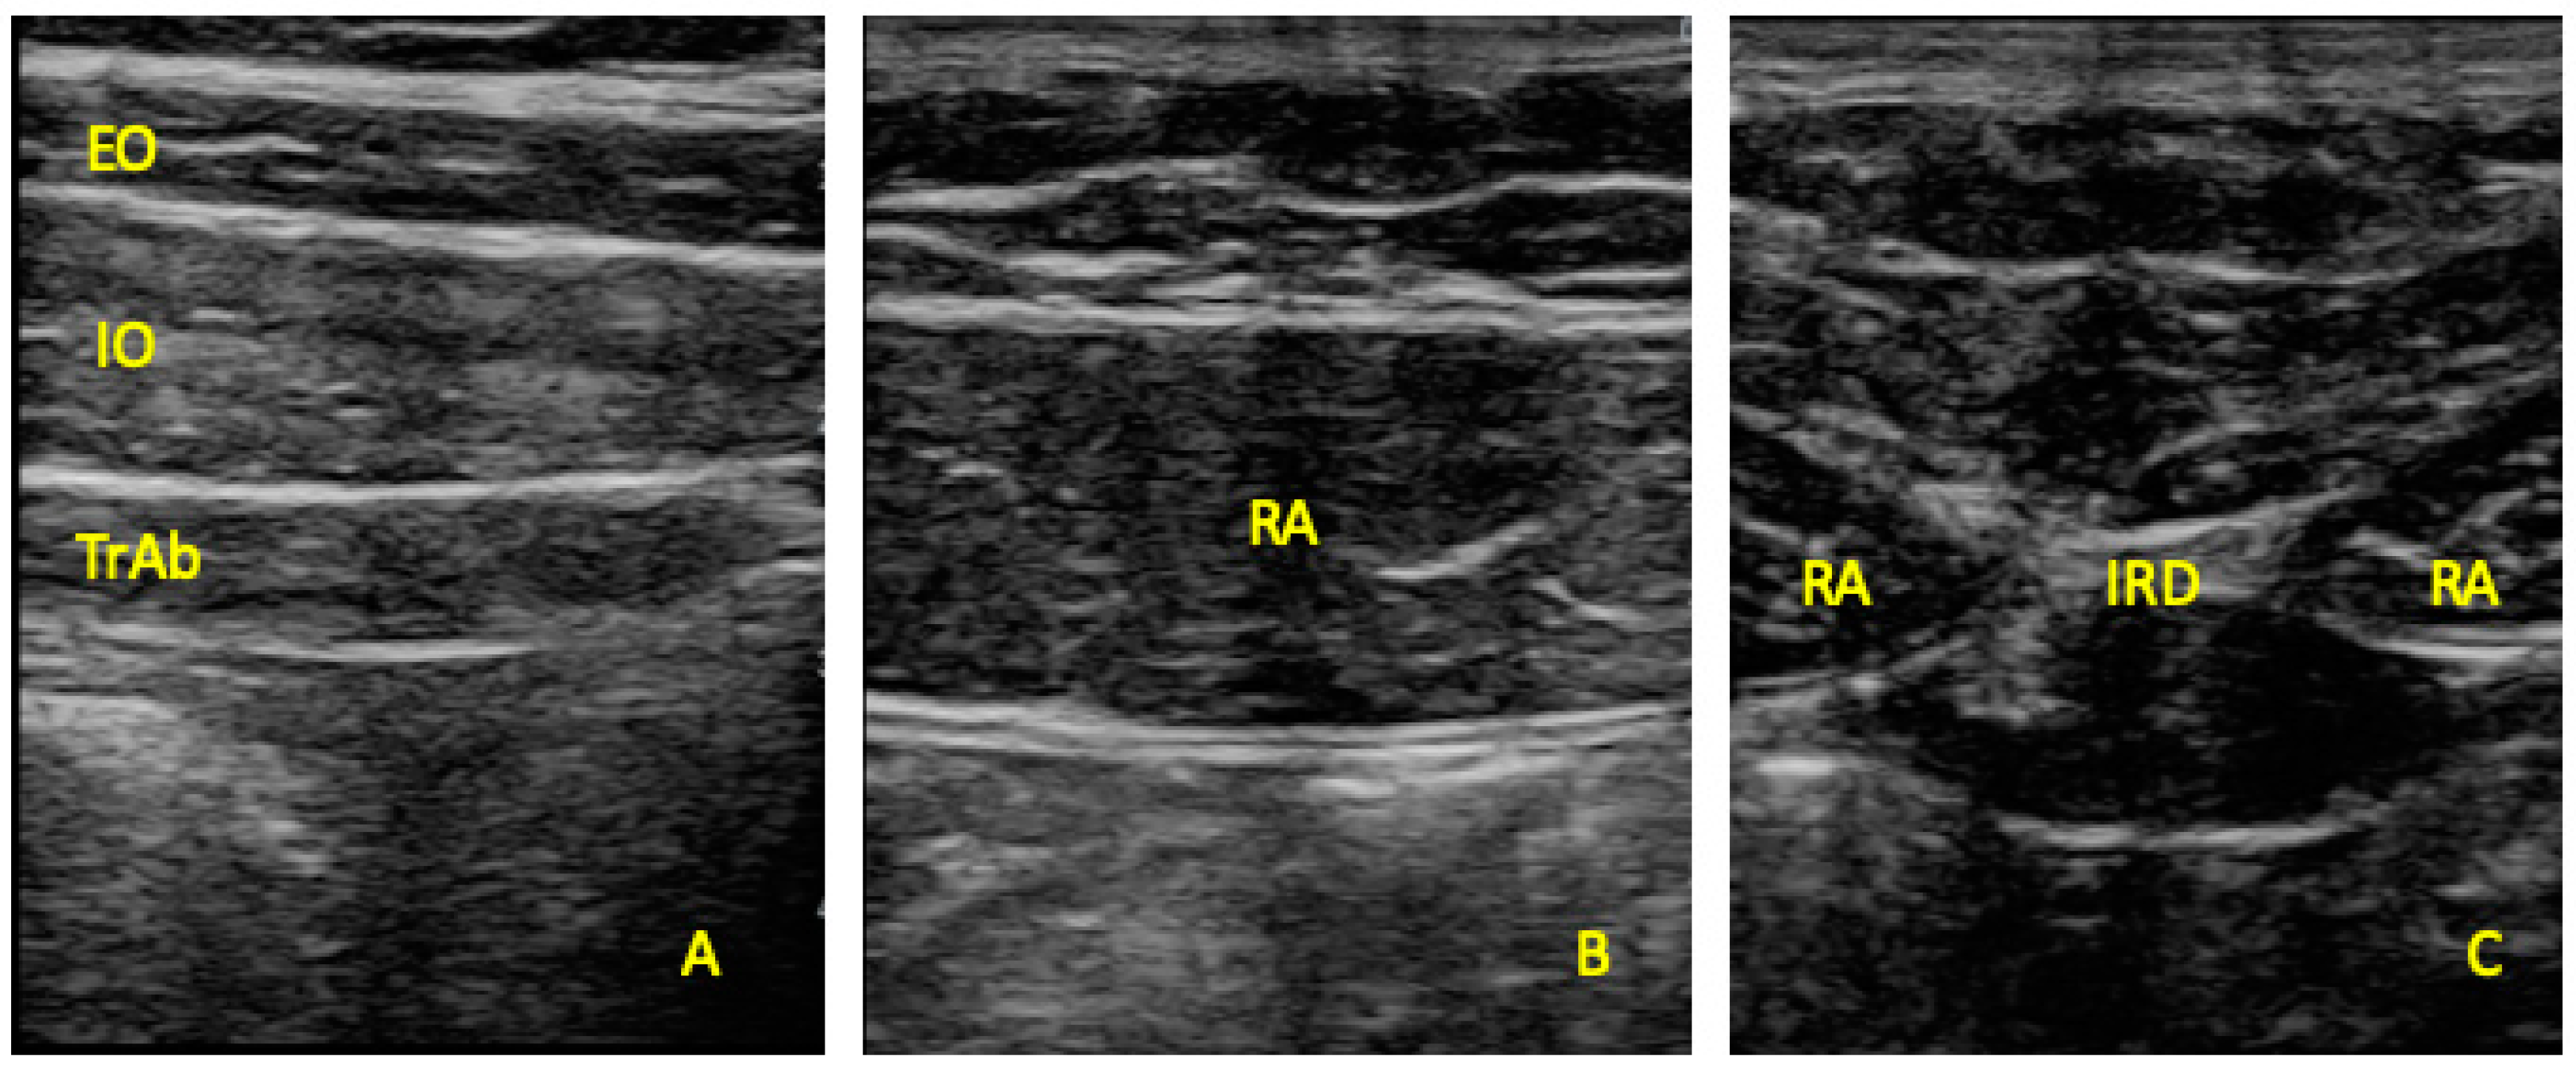

Ultrasonography was developed with a LogiQ ultrasound system (GE, Healthcare, UK), with a 4–13 MHz linear transducer (38-mm footprint) for the anterior abdominal wall muscles and with a 2–5.5 MHz convex transducer (38-mm footprint) for the multifidus evaluations. All the evaluations were developed by the same therapist (P.M.L.), with 3 years of experience in ultrasound imaging of the musculoskeletal field. All the images for the anterior abdominal muscles were taken in supine position. The images of the EO, IO, and TrAb muscles was developed by placing the transductor in the mid-axillary line, between the subcostal line and the iliac crest [9] (Figure 1A). For the RA muscle examination, the transducer was placed aligned with the umbilicus, and just under the umbilicus for the IRD evaluation (Figure 1B). Muscle thickness was considered as the distance between the edges of each muscle and IRD was described as the distance between the both RA muscles [9]. For the multifidus muscles examinations patients were placed lying in prone position at rest and during a maximal isometric contraction with the ipsilateral extended lower limb for 5 s. Following the Wallwork et al. [36] guidelines, the transducer locations were identified by palpations of L4–L5 spinous as the reference points. The thickness of the multifidus muscles was considered as the tip of the target zigapophyseal L4–L5 joint to the inside edge of the superior border of the multifidus muscle [36] (Figure 2A). According to Huang et al. [37], the CSA of the multifidus muscle was recorded with the transducer placed on the skin 25-mm distal from the spinous process of L5 and vertical to the spine (Figure 2B).

Figure 1.

Ultrasound imaging thickness for the EO, IO, TrAb (A), RA thickness (B) muscles, and IRD (C). EO, external oblique; IO, internal oblique; TrAb, transversus abdominis; RA, rectus abdominis; IRD, inter-recti distance.